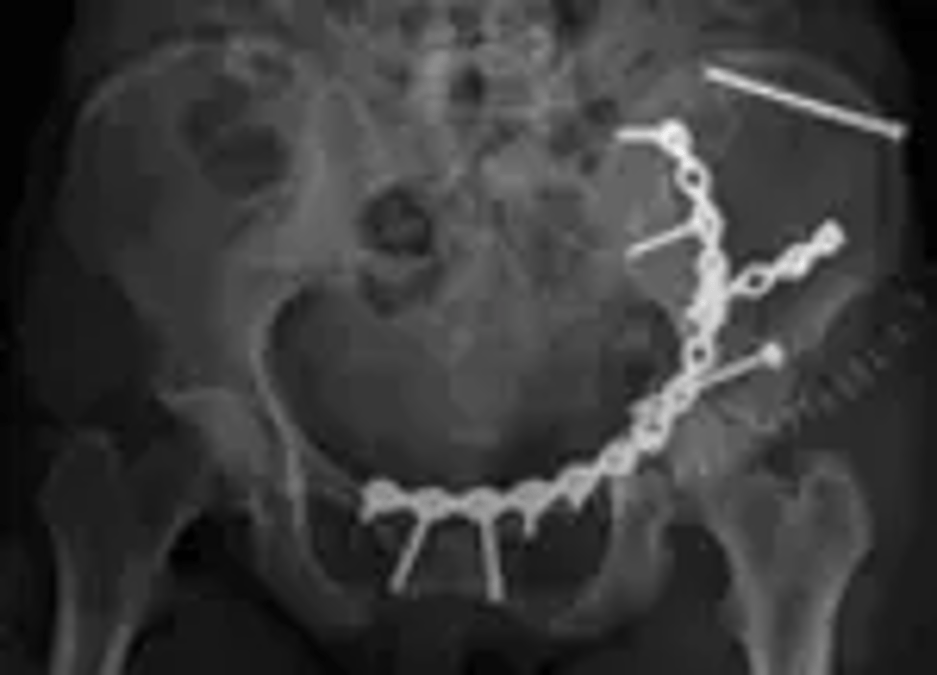

Livskvaliteten relativt god efter svåra bäckenskador

På Akademiska sjukhuset opereras 50-70 personer varje år för svåra bäckenskador, vilket är mer än hälften av alla i landet. De skadade kommer från hela landet, många transporteras hit i ambulanshelikopter. Förutom trafikolyckor är fall från hög höjd, exempelvis från stegar eller på byggarbetsplatser de vanligaste skadeorsakerna